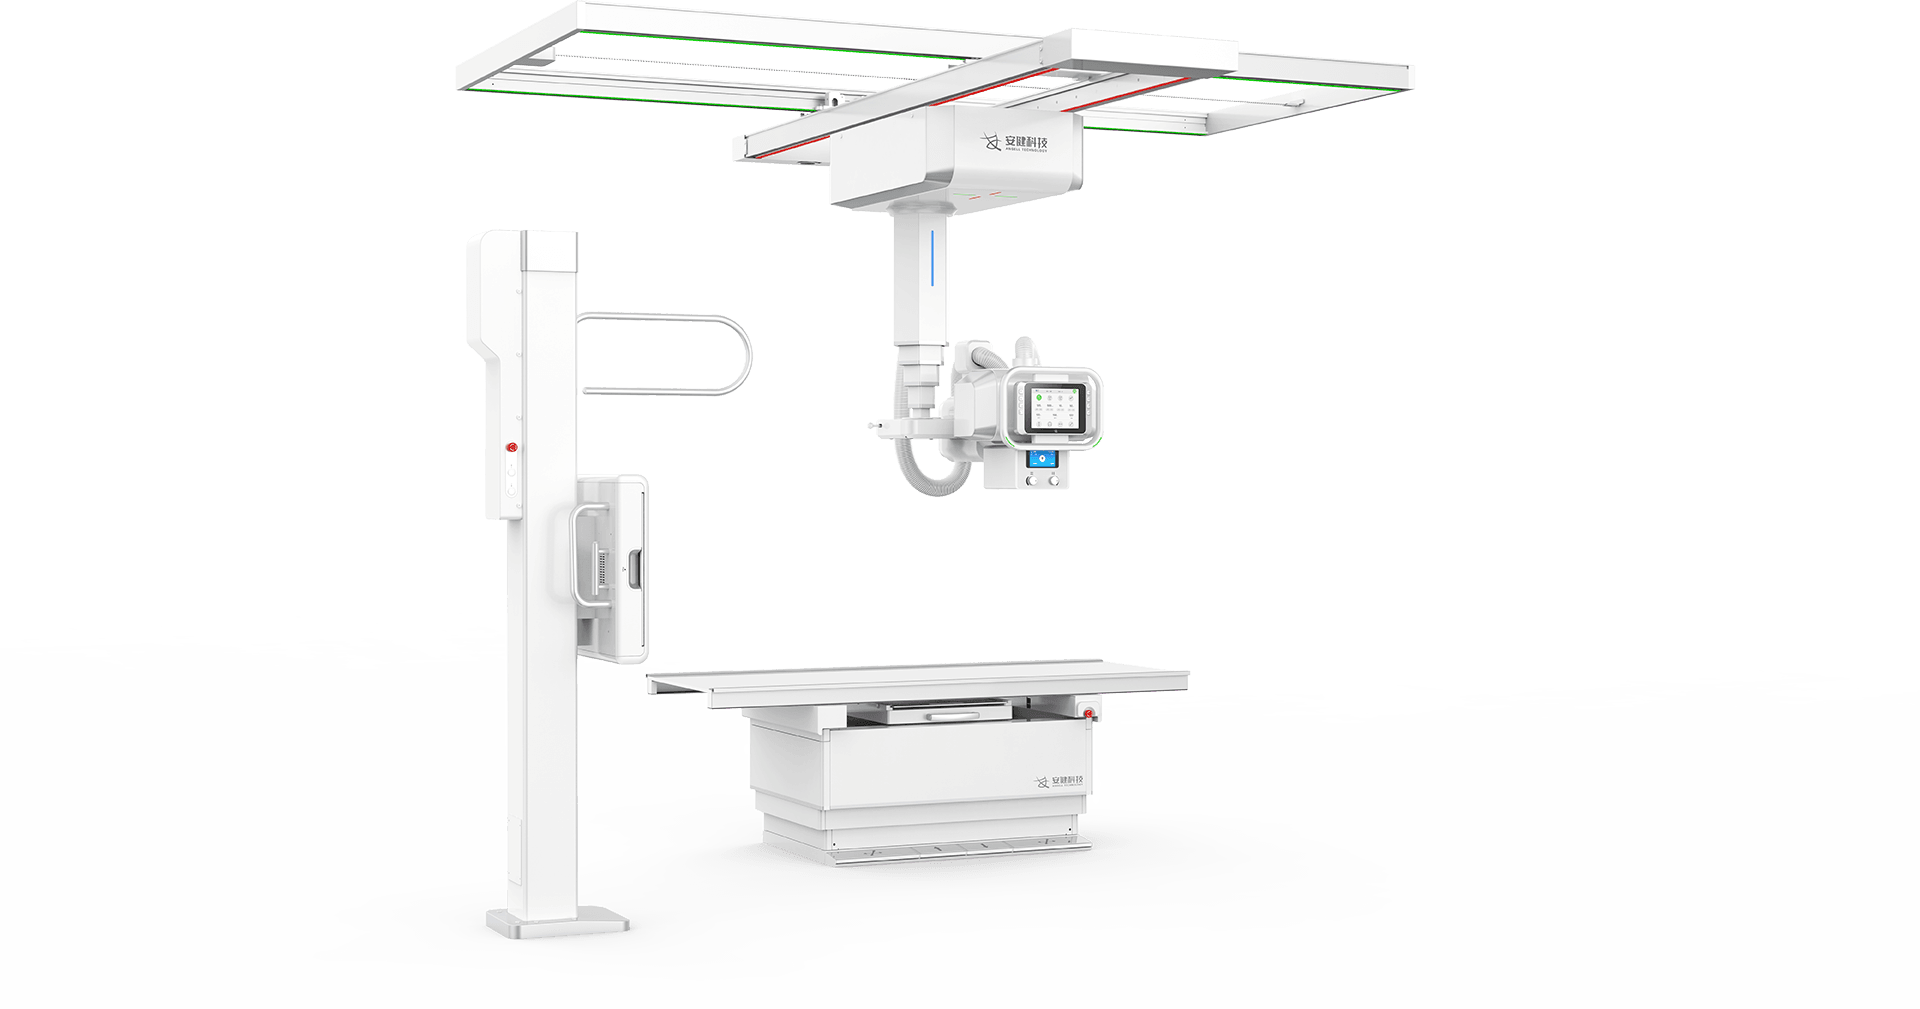

4DК®ЦбБЄ¶ЇФЛ¶ЇПµНі

¶а№¦ДЬРьµхКЅ»ъРµФЛ¶ЇЈ¬И«ЖЅєвОИ¶ЁРФЙијЖЈ¬4DК®ЦбБЄ¶ЇјјКхЈ¬»ъјЬФЛ¶ЇЧФИзЖЅОИЈ¬

ЕдєПµз¶ЇЙэЅµґІј°¶а№¦ДЬБўКЅЙгУ°јЬЈ¬ЗбЛЙВъЧгБЩґІИ«МеО»ЙгУ°РиЗуЎЈ

Зт№ЬОеПтКЦЧФТ»МеФЛ¶Ї

ІЙУГКЦ¶ЇУлµз¶ЇТ»Ме»ЇЙијЖЈ¬ІўѕЯ±ёёРУ¦Зэ¶Ї№¦ДЬЈ¬

Т»јьЅвЛшјґїЙЗбЛЙІЩїШЗт№ЬµДИ«ПтФЛ¶ЇЎЈ -

МЅІвЖчЎўЗт№ЬЛ«ПтЧФ¶ЇёъЧЩ

МЅІвЖчУлЗт№ЬїЙКµПЦЛ«ПтЧФ¶ЇёъЧЩЈ¬

БўОФО»ёЯѕ«¶ИКµК±Н¬ІЅЈ¬ґу·щМбёЯБЩґІјмІйР§ВКЎЈ -

µз¶ЇЙэЅµґІ

і¬ґуРРіМФЛ¶Ї·¶О§Ј¬Бй»оУ¦¶Ф¶щНЇЎўАПИЛЎўНвЙЛ»јХЯЙППВґІЎЈ

Ед±ёЗ¶ИлКЅёРУ¦ЅвЛшПµНіЈ¬ЗбЛЙµчЅЪґІёЯІўУРР§±ЬГв»јХЯО󴥡Ј